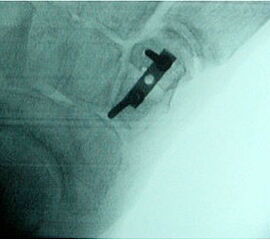

Rupturierte Tibialis posterior Sehne in den coronaren, protonensensitiven Schichten. Bei diskreten Läsionen erhöht die Gabe von Kontrastmittel die Beurteilbarkeit.

Abbildung 6g

Die Magnet-Resonanz-Tomographie (MRT) eignet sich besonders zur Darstellung der Tenosynovitis und Degeneration der Tibialis posterior Sehne. Hinsichtlich Sensitivität und Spezifität ist das MRT dem CT insbesondere bei Sehnenlängsrupturen überlegen 23. Die normale Sehne erscheint auf dem MRT mit schwarzem, homogenem Signal und ovaler Form, zwei bis dreimal dicker als die Sehne des M. flexor digitorum longus. Ein schmaler Flüssigkeitsaum < 1-2 mm ist physiologisch. Bei der Tenosynovitis ist der Saum deutlich breiter und neben dem Ödem in der Sehnenmatrix am besten auf den T2-Wichtungen zu erkennen. Strukturelle Veränderungen der Sehnenmatrix, wie z.B. Partial- oder Längsrupturen sind besser auf den T1-Wichtungen zu sehen. Nach der Sehnenhypertrophie im Stadium I der Erkrankung kommt es jeweils mit wenig oder keiner Begleitentzündung im Stadium II zur Elongation und Abnahme des Sehnendurchmessers und im Stadium III zur Ruptur, welche im MRT gut ersichtlich sind. Hingegen finden sich mit zunehmender Dauer der Erkrankung Entzündungszeichen infolge fibulocalcanearen Impingements und lateral betonter OSG-Degeneration und Arthrose v.a. auf den T2-Wichtungen.